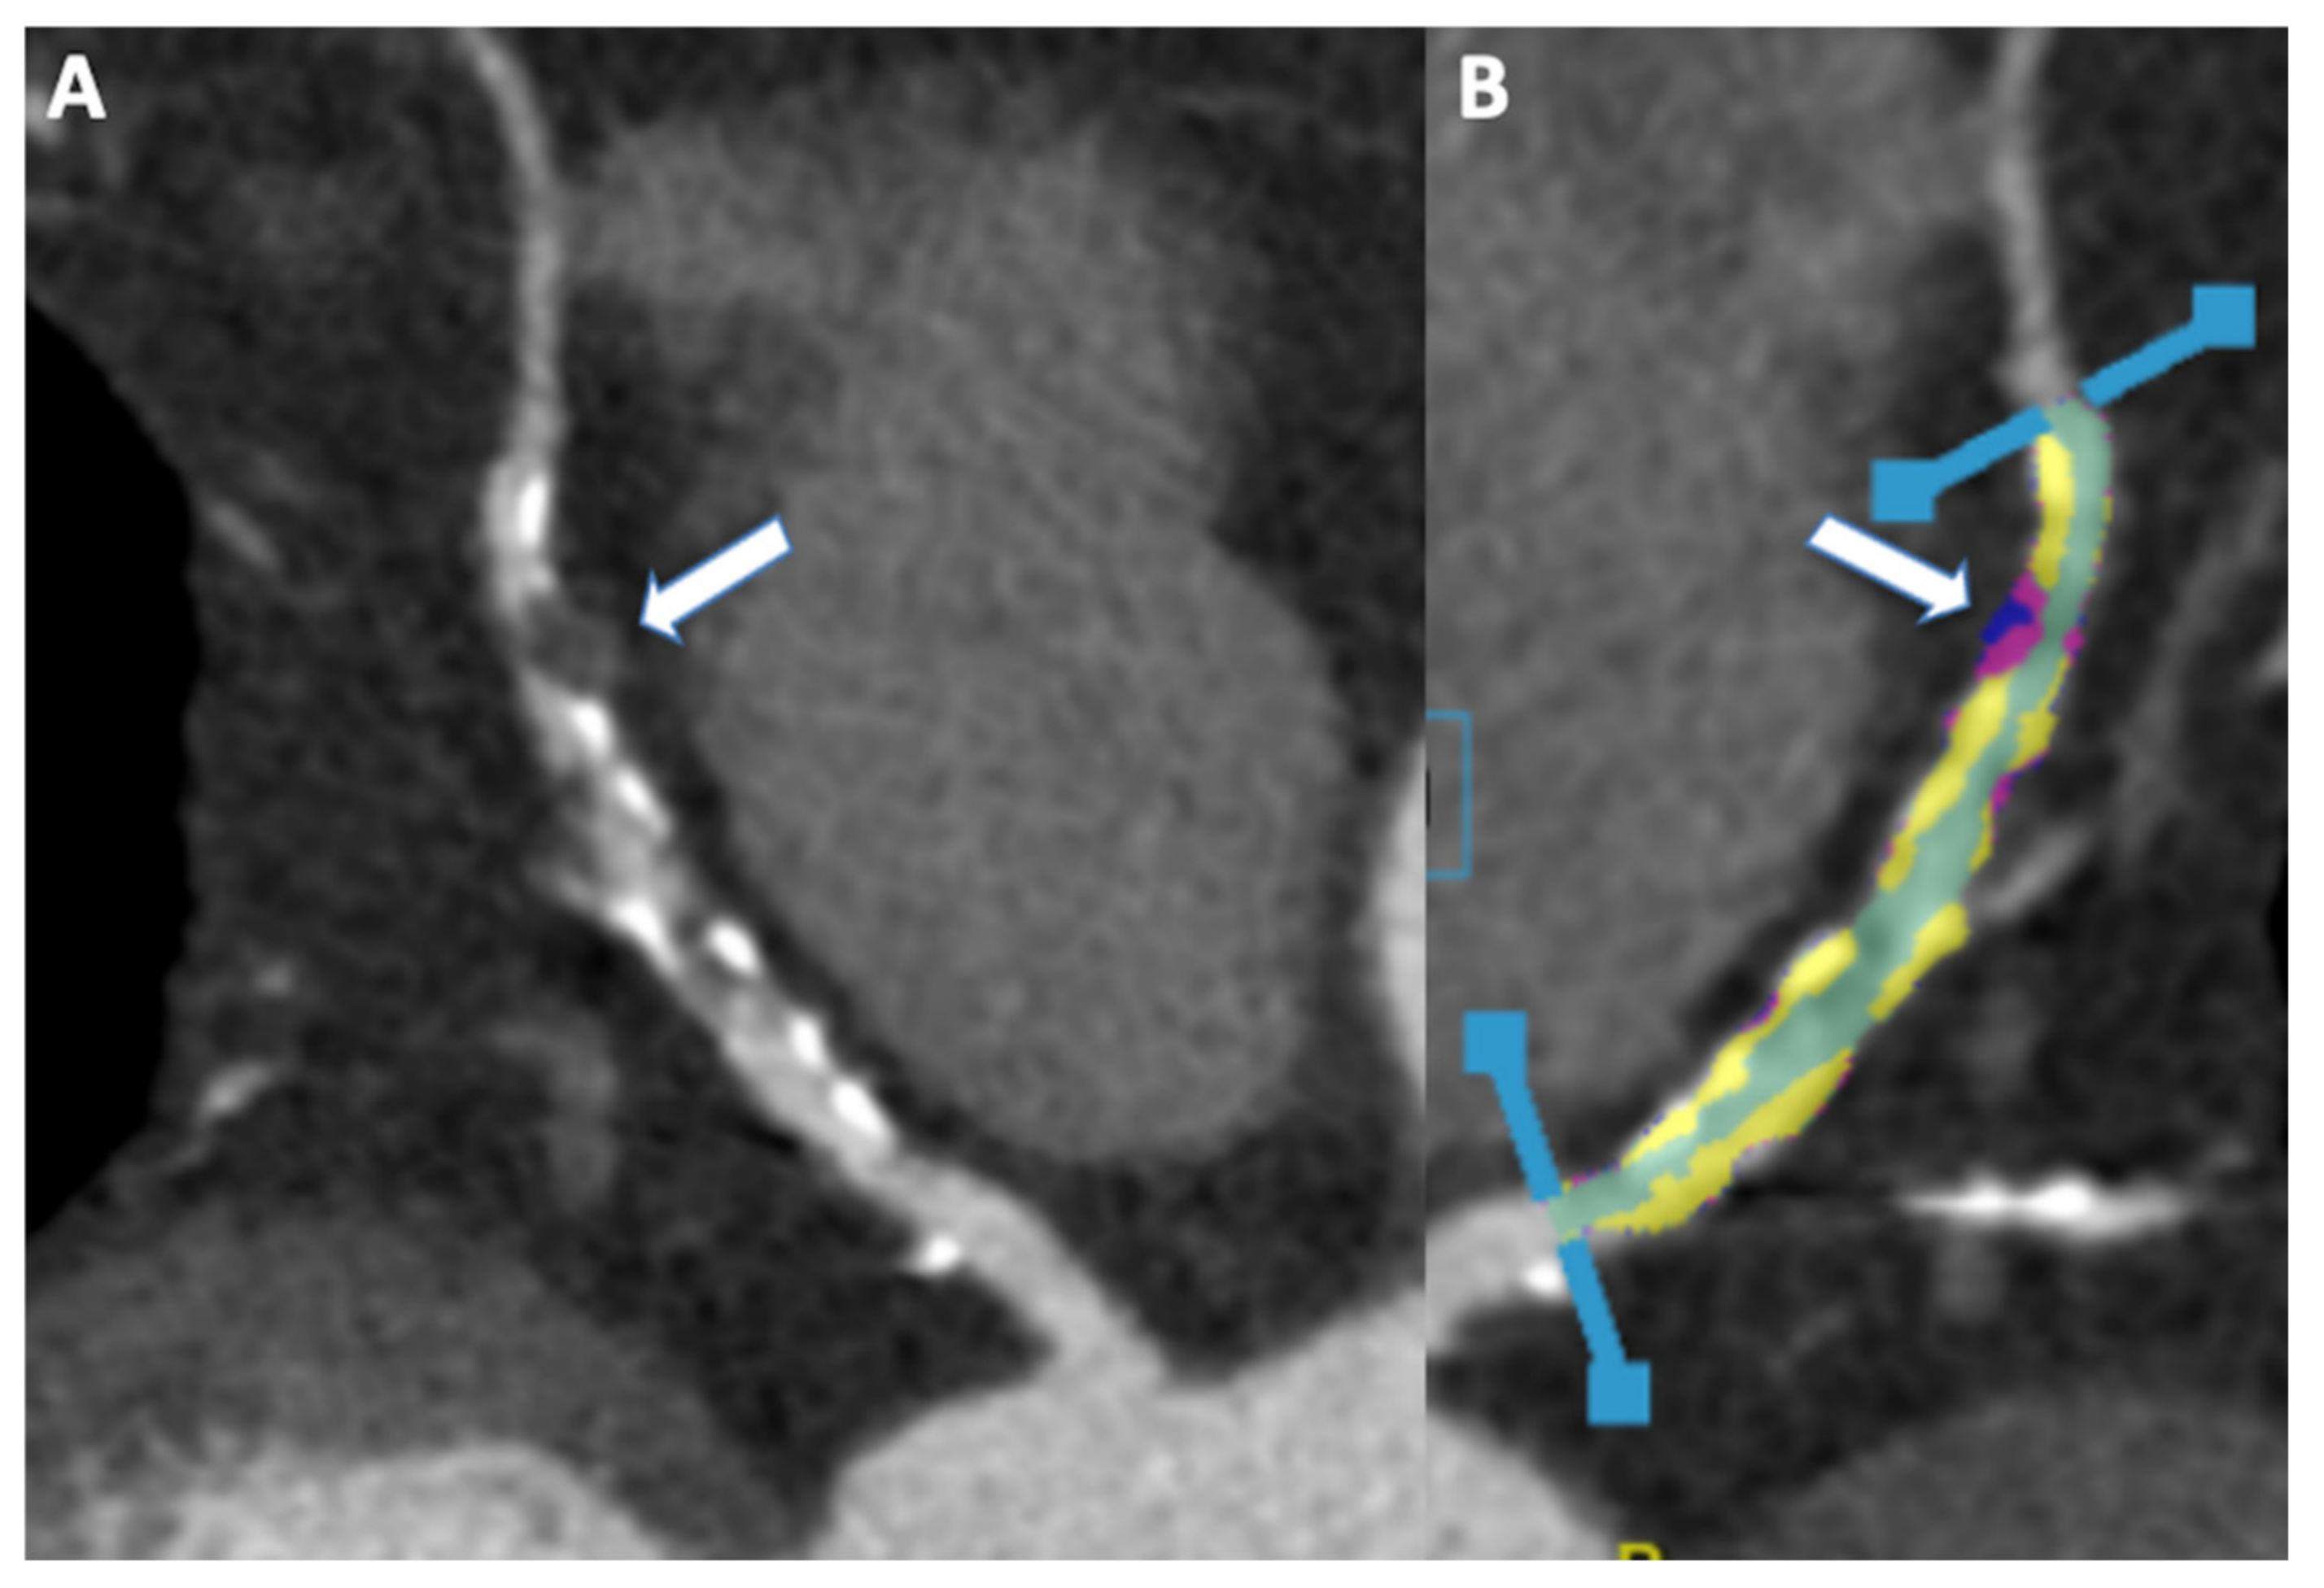

- Van den Hoogen, I.J.; Gianni, U.; Al Hussein Alawamlh, O. What atherosclerosis findings can CT see in sudden coronary death: Plaque rupture versus plaque erosion. J. Cardiovasc Comput. Tomogr. 2020, 14, 214–218. [Google Scholar] [CrossRef]

- Motoyama, S.; Ito, H.; Sarai, M.; Kondo, T.; Kawai, H.; Nagahara, Y.; Harigaya, H.; Kan, S.; Anno, H.; Takahashi, H.; et al. Plaque Characterization by Coronary Computed Tomography Angiography and the Likelihood of Acute Coronary Events in Mid-Term Follow-Up. J. Am. Coll. Cardiol. 2015, 66, 337–346. [Google Scholar] [CrossRef]

- Chang, H.-J.; Lin, F.Y.; Lee, S.-E.; Andreini, D.; Bax, J.; Cademartiri, F.; Chinnaiyan, K.; Chow, B.J.; Conte, E.; Cury, R.C.; et al. Coronary Atherosclerotic Precursors of Acute Coronary Syndromes. J. Am. Coll. Cardiol. 2018, 71, 2511–2522. [Google Scholar] [CrossRef]

- Williams, M.C.; Moss, A.J.; Dweck, M.; Adamson, P.D.; Alam, S.; Hunter, A.; Shah, A.S.; Pawade, T.; Weir-McCall, J.R.; Roditi, G.; et al. Coronary Artery Plaque Characteristics Associated with Adverse Outcomes in the SCOT-HEART Study. J. Am. Coll. Cardiol. 2019, 73, 291–301. [Google Scholar] [CrossRef]